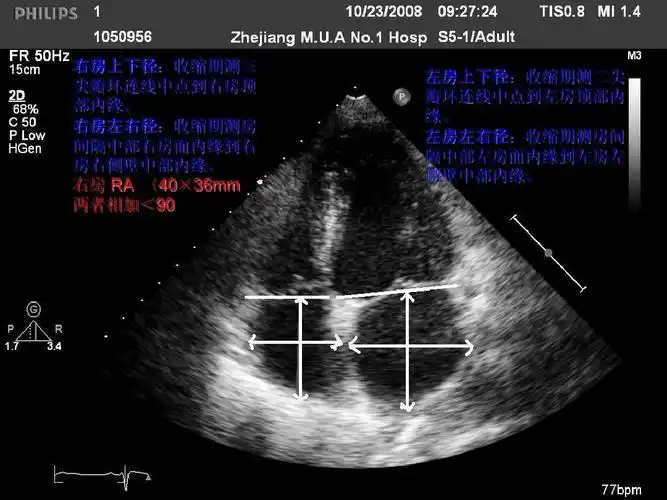

心脏彩超能检查出什么?

心脏彩超